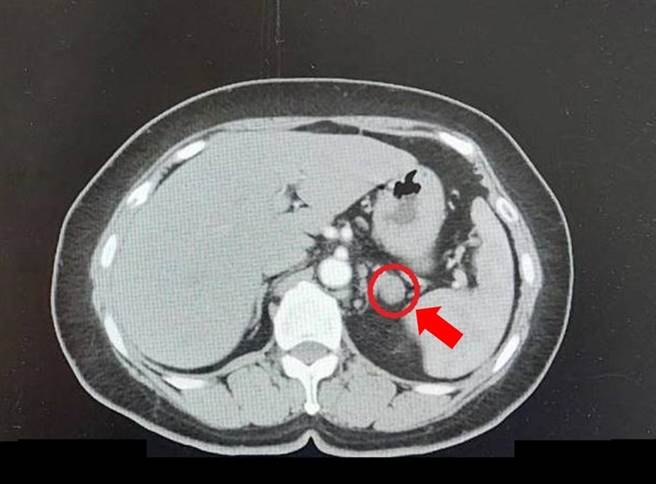

邱女因腎上腺腫瘤(紅圈處)影響血壓問題,手術治療後獲得大幅改善。(大千醫院提供/謝明俊苗栗傳真)

大千醫院腎臟內科醫師陳孟財表示,造成邱女低血鉀原因,是因為大量的鉀離子從腎臟流失,同時血液中的腎素出現低下且合併有醛固酮上升的情形,因此懷疑她有腎上腺腫瘤。經透過腹部電腦斷層檢查,果然在左側腎上腺發現一顆約1.9x1.5公分的腫瘤,所幸經手術治療後,邱女士低血鉀的問題順利解決,高血壓的控制也獲得很大的改善,目前只需要服用1-2種血壓藥即可。